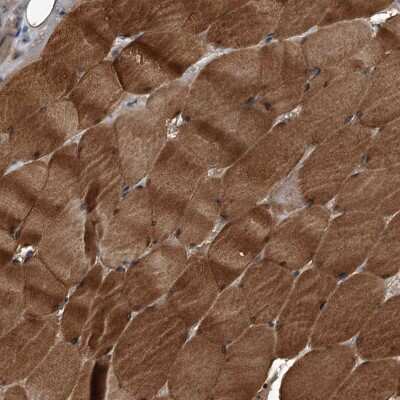

Immunohistochemistry-Paraffin: Kir2.1 Antibody [NBP1-87709]

Immunohistochemistry-Paraffin: Kir2.1 Antibody [NBP1-87709] - Staining of human heart muscle shows strong cytoplasmic positivity in cardiomyocytes.